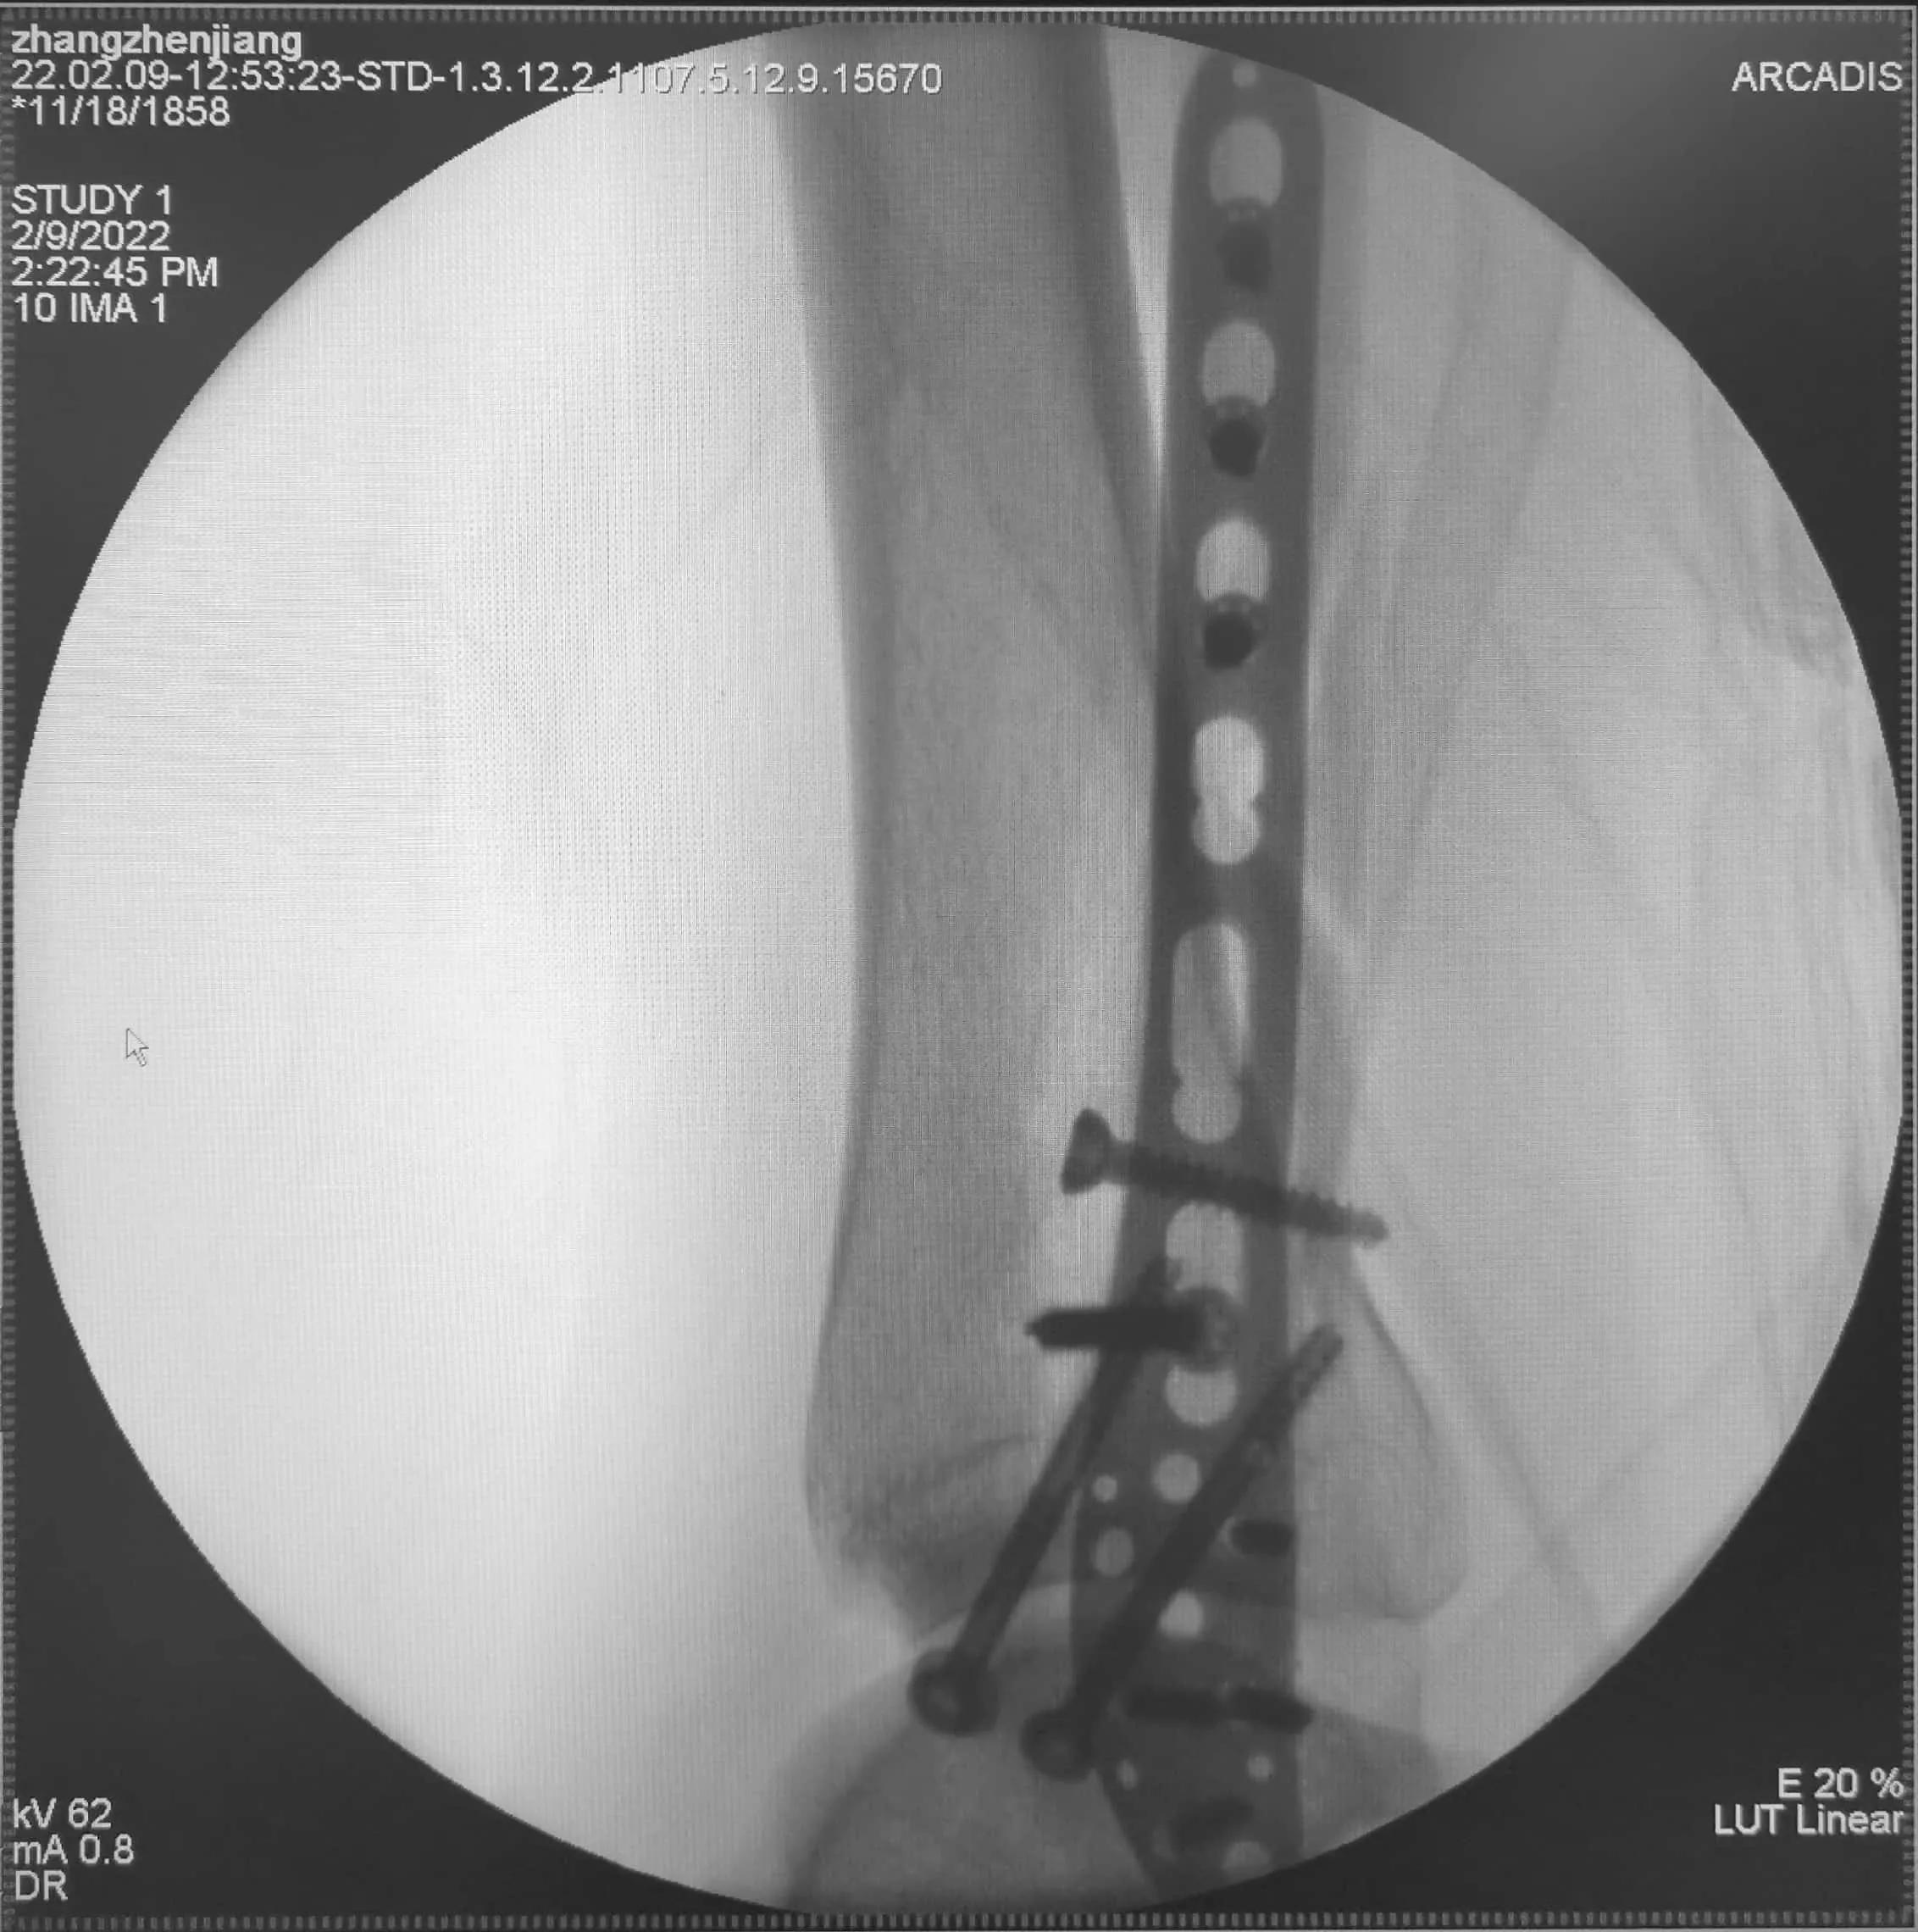

2022年2月9日手术中照片

幸运的是,今天手术踝关节骨折获得了满意的复位!